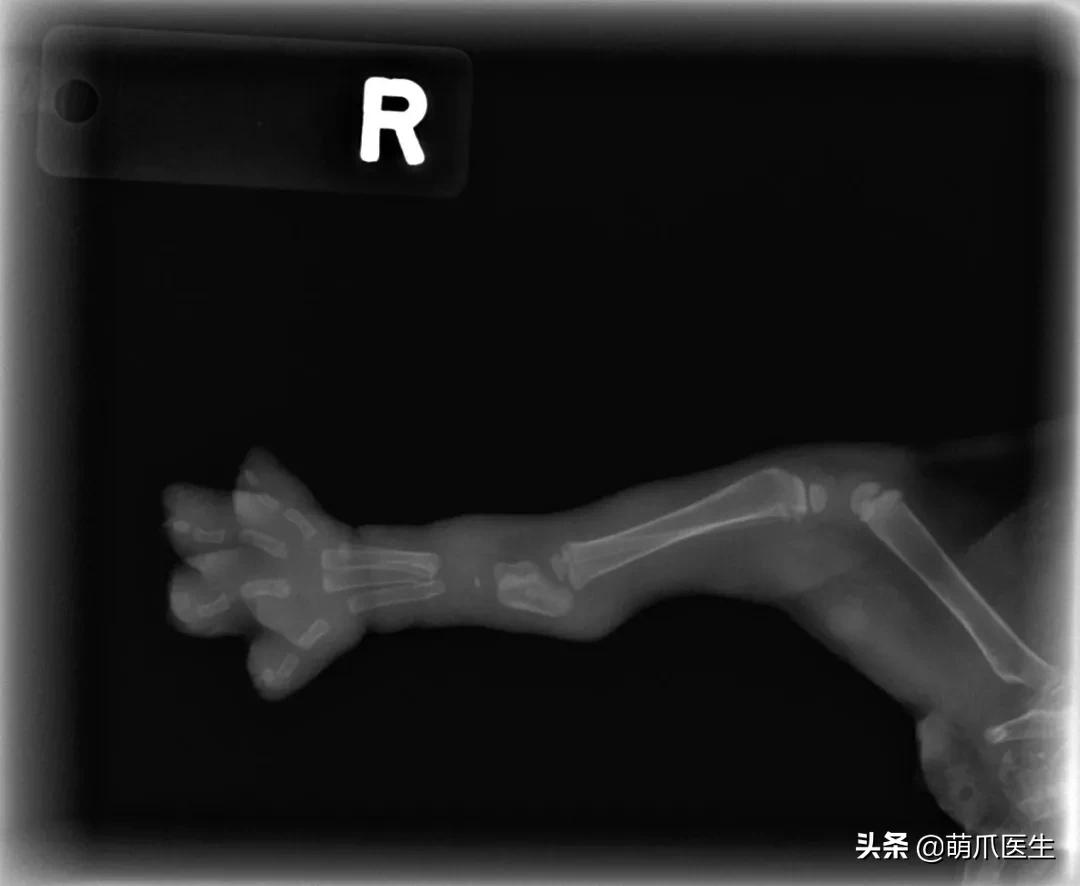

为了证明自己没有作假,LinzerBinzer不得不上传了小猫咪另一只脚的X光片,看上去确实是同样的效果……

小猫年龄只有5~6周大,骨骼系统还没有完全发育。此时它骨头之间相连的结缔策划在X射线下是透明的,所以看上去才会如此“不真实”。

网友提供了一只仅出生3天的狗狗X光片

另一派则认为,从细节上看,这是真实的X光片。 成像如此是因为幼猫骨化不完全。

还有医生提供了 4周大的猫咪X光作参考 。